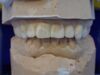

Mann kann hier sehr gut an den beiden Punkten der distalen Dreipunktabstützung erkennen, mit welch hoher Passgenauigkeit die Zentrikplatten auf die Gipszähne der Meistermodelle aufgebacht werden können und müssen.

Es ist einer dieser Detailpunkte, der darüber entscheidet, mit welcher Anfangspassgenauigkeit ein 'A'ufbissbehelf am Ende eines langwierigen Arbeitsprozesses in der Mundhöhle des Patienten eingeglidert werden kann.